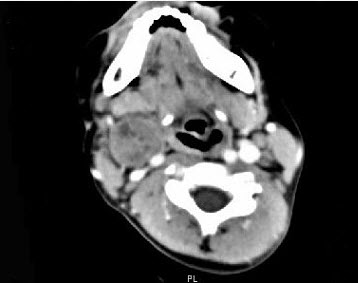

女,4岁,右侧颈部可扪及一包块约两个月,无热无痛,CT如图所示,最可能的诊断为()。

A、咽旁血管外皮瘤

B、咽旁副神经节瘤

C、咽旁脓肿

D、咽旁神经纤维瘤

E、咽旁小唾液腺混合瘤

D